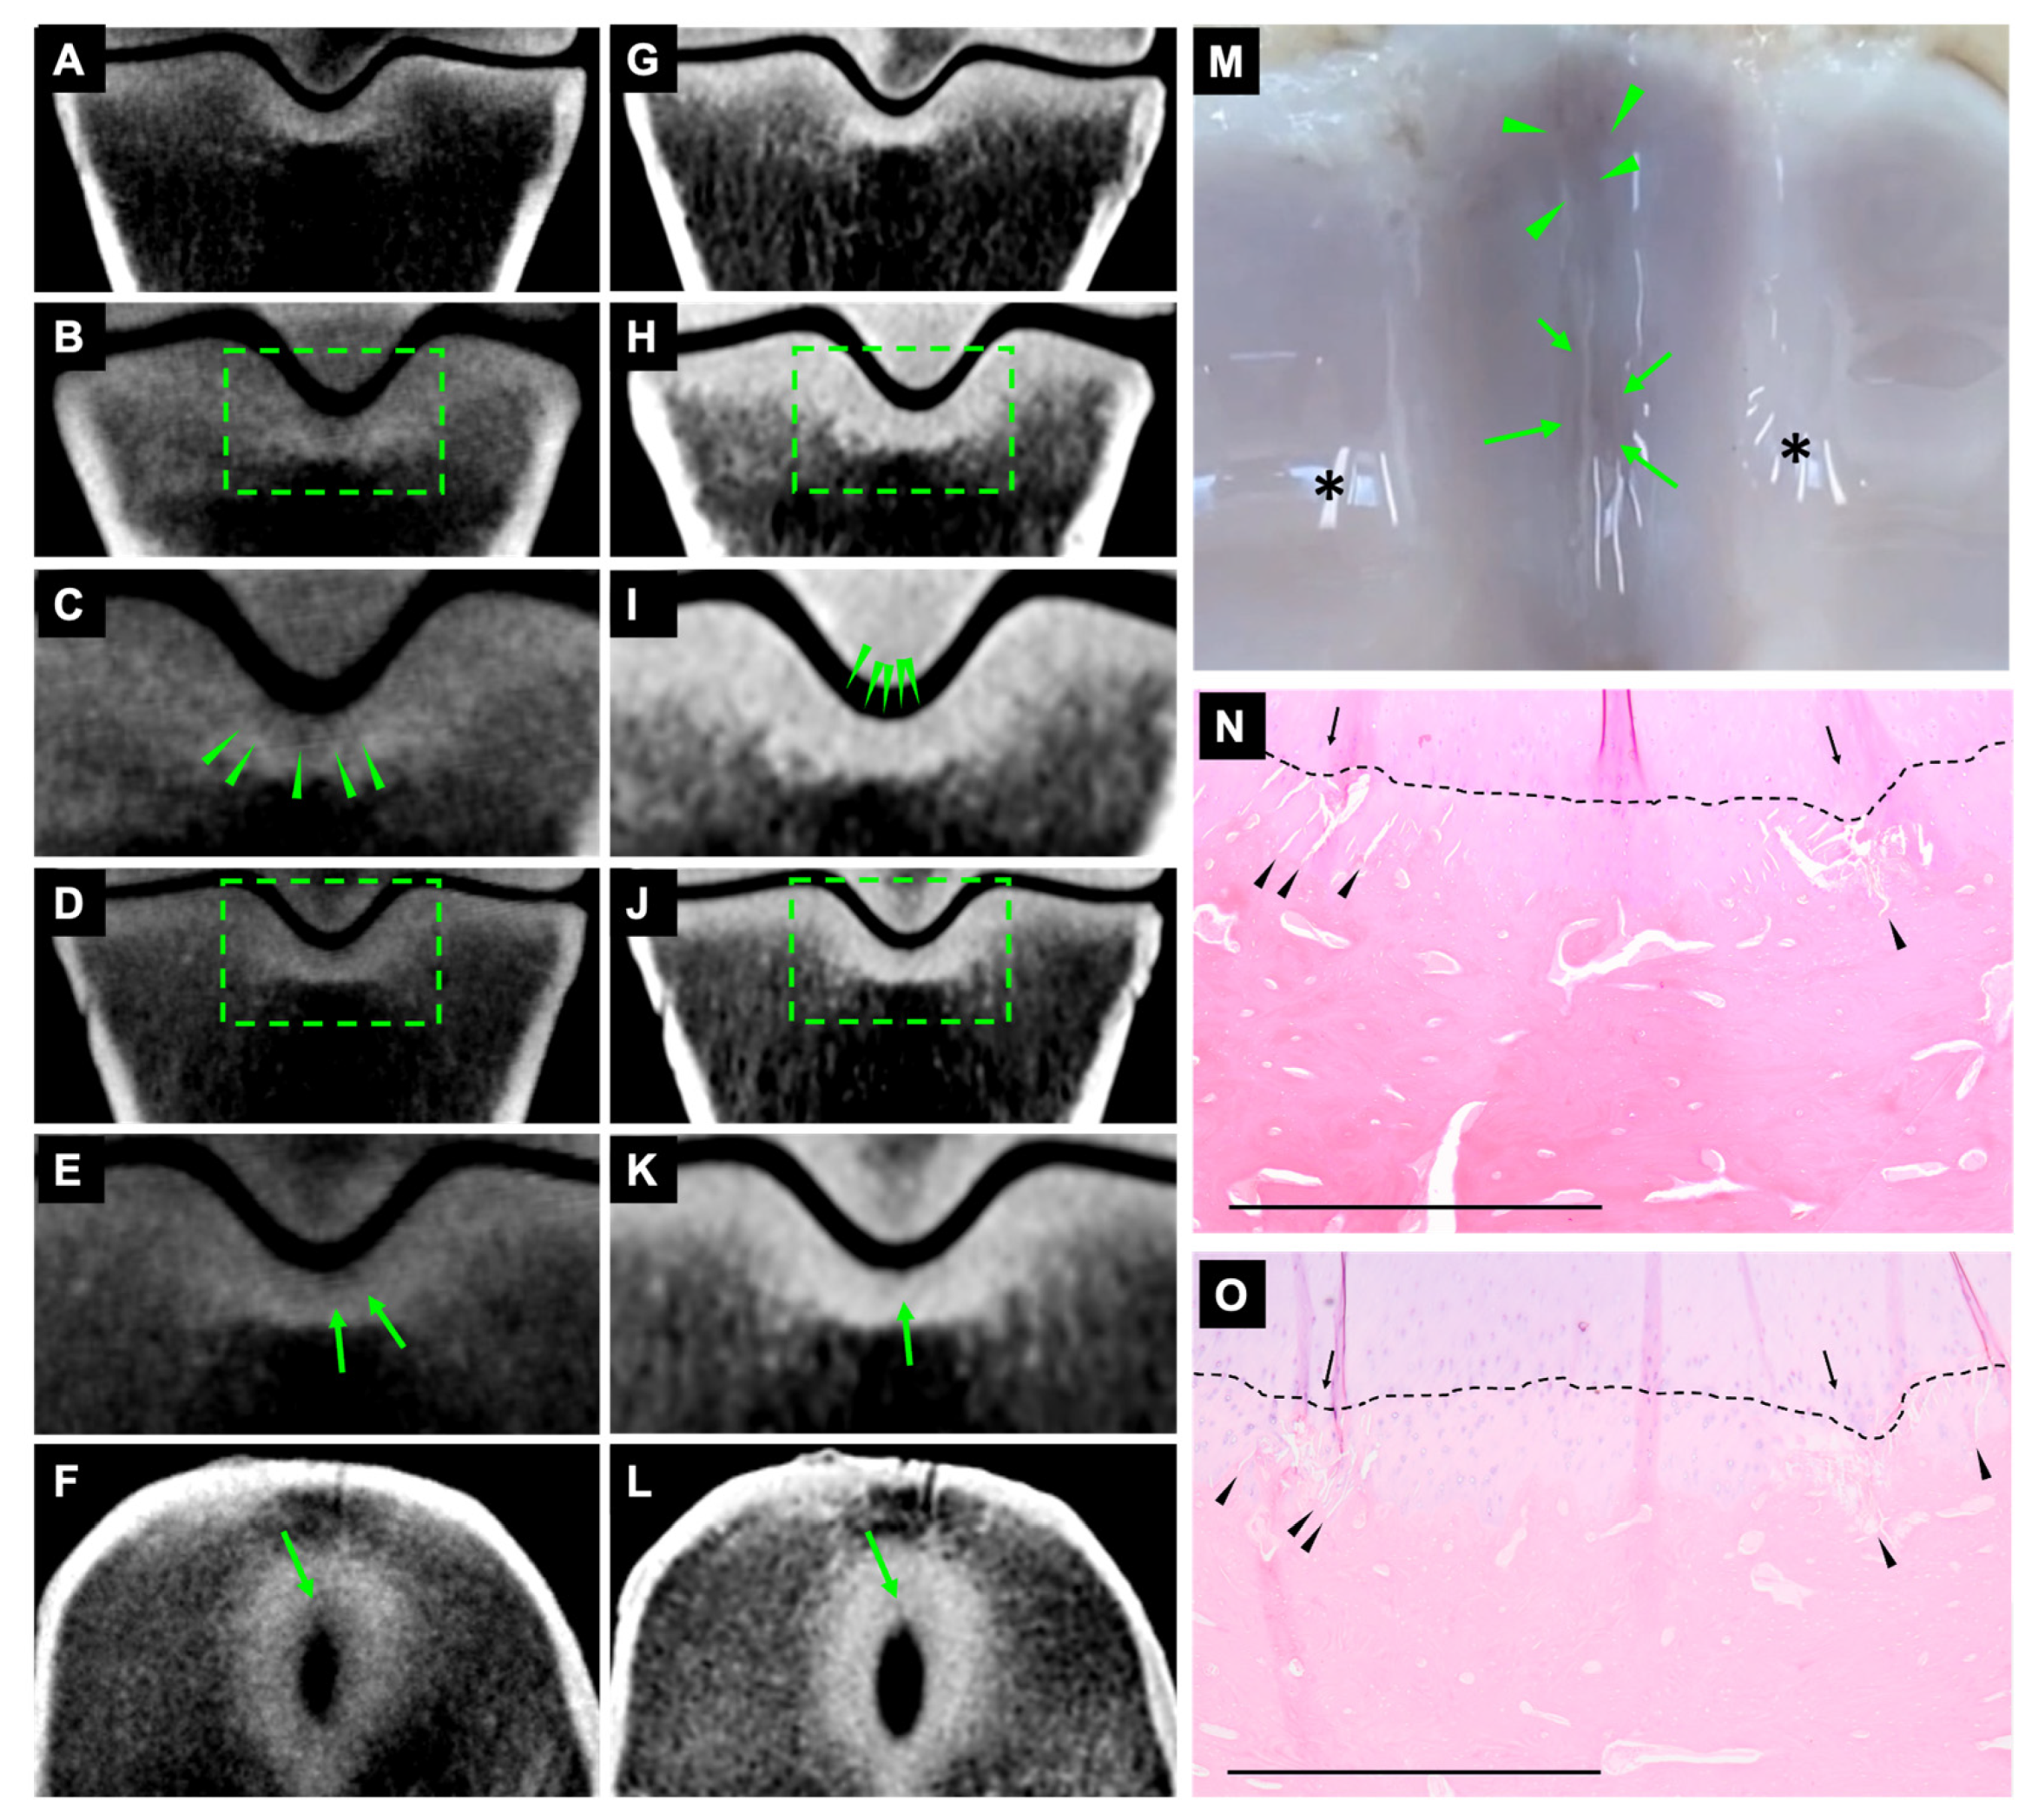

On CBCT and FBCT images, 34 fissures were identified as subtle striated hypoattenuated lines in the subchondral bone (Figure 2 and Figure 3). The fissures were most clear on dorsal orientation and appeared as very subtle, hypoattenuating lines on transverse orientation (Figure 3).

Figure 3.

Fissures at the dorsal and middle aspects of the sagittal groove. Lateral is to the right. CBCT (A–F) and FBCT (G–L) dorsal and transverse orientation. Images (A,G) are diagrams showing the normal appearance of dorsal sections, without fissures in the sagittal groove. Images (C,I) are magnifications of the selected area on images (B,H). Striated hypoattenuating lines on CBCT and subchondral outline irregularity on FBCT at the dorsal aspect of sagittal groove (arrowheads; (C,I)). Images (E,K) are magnifications of the selected area on images (D,J). Striated hypoattenuating lines in the subchondral bone on CBCT and FBCT at the middle aspect of sagittal groove (arrow; (E,K)). A subtle, hypoattenuating line was seen in the transverse orientation (arrow; (F,L)). Macroscopic appearance of fissures at the dorsal and middle aspects of sagittal groove with subchondral discolouration (arrowheads and arrows; (M)). Artefacts of light reflection (*). Microscopic appearance of fissures at the dorsal (N) and middle (O) aspects of sagittal groove. Microcracks in the calcified cartilage and subchondral bone plate appeared as oblique striated linear lesions and some were coalescing (arrowhead; (N,O)). Tidemark incongruence (arrow, (N,O)). Interface between articular hyaline cartilage and calcified cartilage (dotted lines, (N,O)). Scale bar = 1 mm.